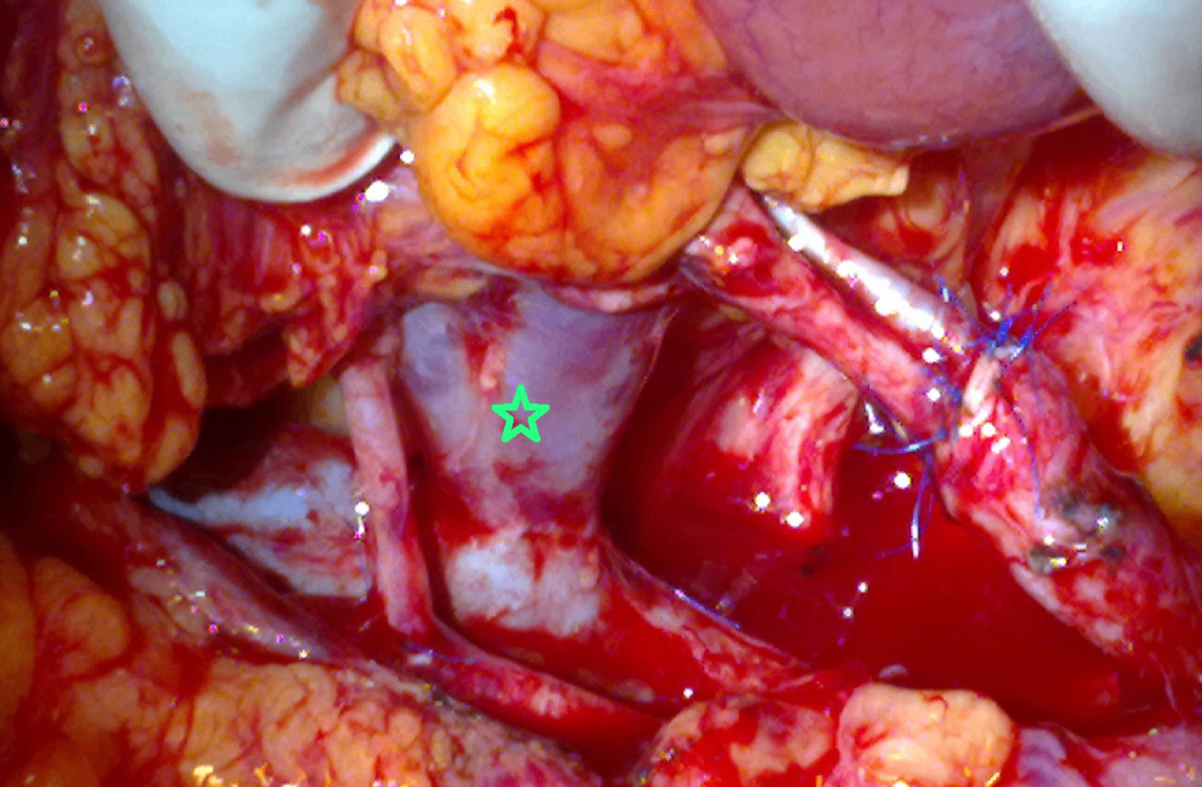

신장이식수술 과정에서 이식신을 수혜자의 체내에 위치시킨 후 사진이다. 가장 먼저 연결하는 구조물(☆)은 무엇인가?

• 신장 이식 과정에서 혈관 문합은 renal vein-external iliac vein 및 renal artery-internal/external iliac artery 의 end-to-side anastomosis가 선호된다.

• 문합 순서는 정맥 → 동맥의 순서가 일반적이나 anastomosis site, graft position, vessel length 등의 요소를 고려하여 동맥을 먼저 문합하기도 한다.

• 사진에 표시된 구조물은 직경이 비교적 크고 검붉은 색을 띄므로 정맥으로 판단된다 (동맥은 정맥보다 근육층이 두꺼워서 희고 탄력있게 관찰됨).

• 보편적인 문합 순서와 육안상의 특징을 종합하면 묻고 있는 구조물은 신정맥으로 보인다.

• 요관: 빠른 재관류가 이식신의 생존에 중요하므로 ureter-bladder 문합보다 혈관 문합을 먼저 시행한다.